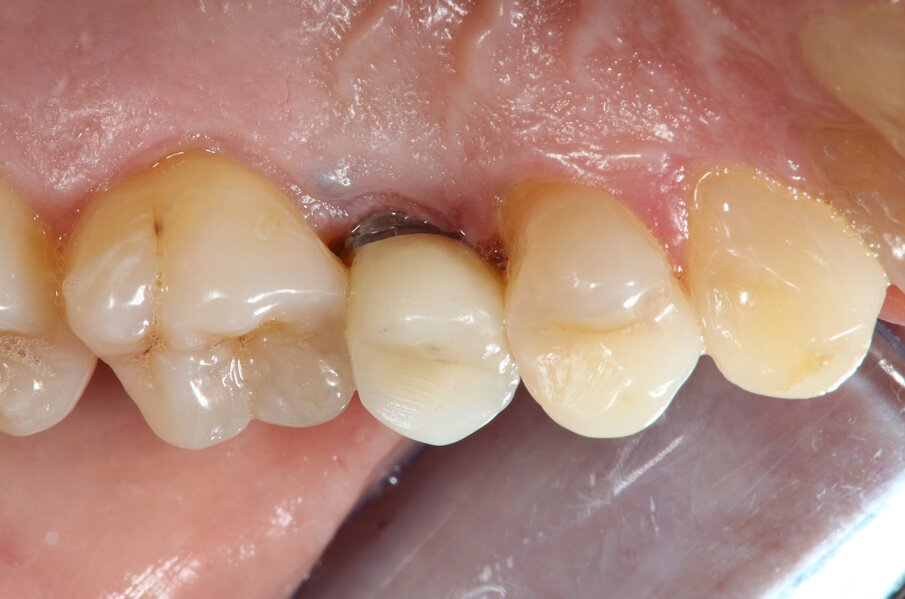

Quinta e sesta seduta A 90 gg si effettua seduta di richiamo con deplaquing, privilegiando l’impiego di polvere di glicina con sistema air polishing (CombiTouch Mectron Spa) con multidirezionalità del getto prima in senso apico-coronale, poi in direzione corono marginale e infine perpendicolare alla superficie implantare esposta, con l’obiettivo di decontaminarla al meglio, senza ledere i tessuti circostanti. A 6 mesi dal baseline (t4) si esegue la rivalutazione. Vengono eseguite fotografia e rx endorale del sito di controllo (Figg. 5, 6). All’esame visivo e palpativo i tessuti molli perimplantari si presentano in buono stato, in termini di colore e consistenza. All’esame radiografico si apprezza una remineralizzazione dell’osso. Viene eseguita la terapia professionale mediante la medesima tecnica di air polishing con polveri a bassa granulometria, al fine di disgregare l’eventuale biofilm patogeno, potenziale causa di recidiva. In entrambe le sedute viene eseguito un rinforzo motivazionale.

Fig. 5

Fig. 6

È possibile apprezzare radiograficamente un’aumentata mineralizzazione ossea, con un ulteriore miglioramento rispetto alla prima rivalutazione post-terapia. Questo dato indica la risoluzione dello stato infiammatorio cronico e conferma il buon potenziale rigenerativo della terapia adottata. Contestualmente, all’esame visivo dei tessuti, si osserva un riposizionamento in direzione coronale del tessuto molle, con un aumento dei volumi gengivali rispetto al tempo t4, anch’esso indicativo del potenziale rigenerativo stimolato dalla strategia terapeutica a livello del tessuto connettivo gengivale.